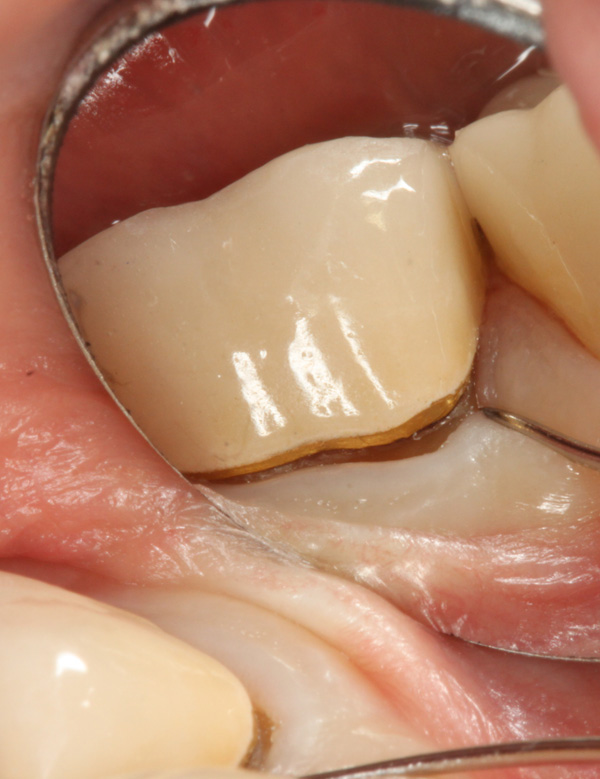

Die Patientin stellt sich mit Zahnschmerzen in der Sprechstunde vor. Die Beschwerden kamen bei Belastung der Molaren unten, links und verschwanden dann nach ein bis zwei Stunden wieder. Die Zähne 34 bis 37 reagierten auf Kälte normal positiv. Zahn 37 war klopfempfindlich. Die Krone auf dem Zahn 37 ist nach Auskunft der Patientin 13 Jahre alt (alio loco). Der Kronenrand zeigt einen sondierbaren Spalt. Wir werden die Krone erneuern.

Detail: